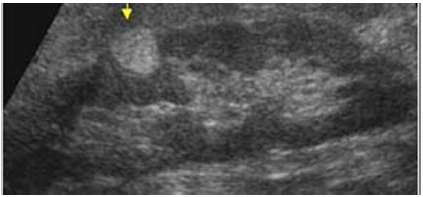

Paciente assintomático, com o seguinte achado na ultrassonografia de abdome. Qual a principal hipótese diagnóstica?

Paciente assintomático, com o seguinte achado na ultrassonografia de abdome. Qual a principal hipótese diagnóstica?